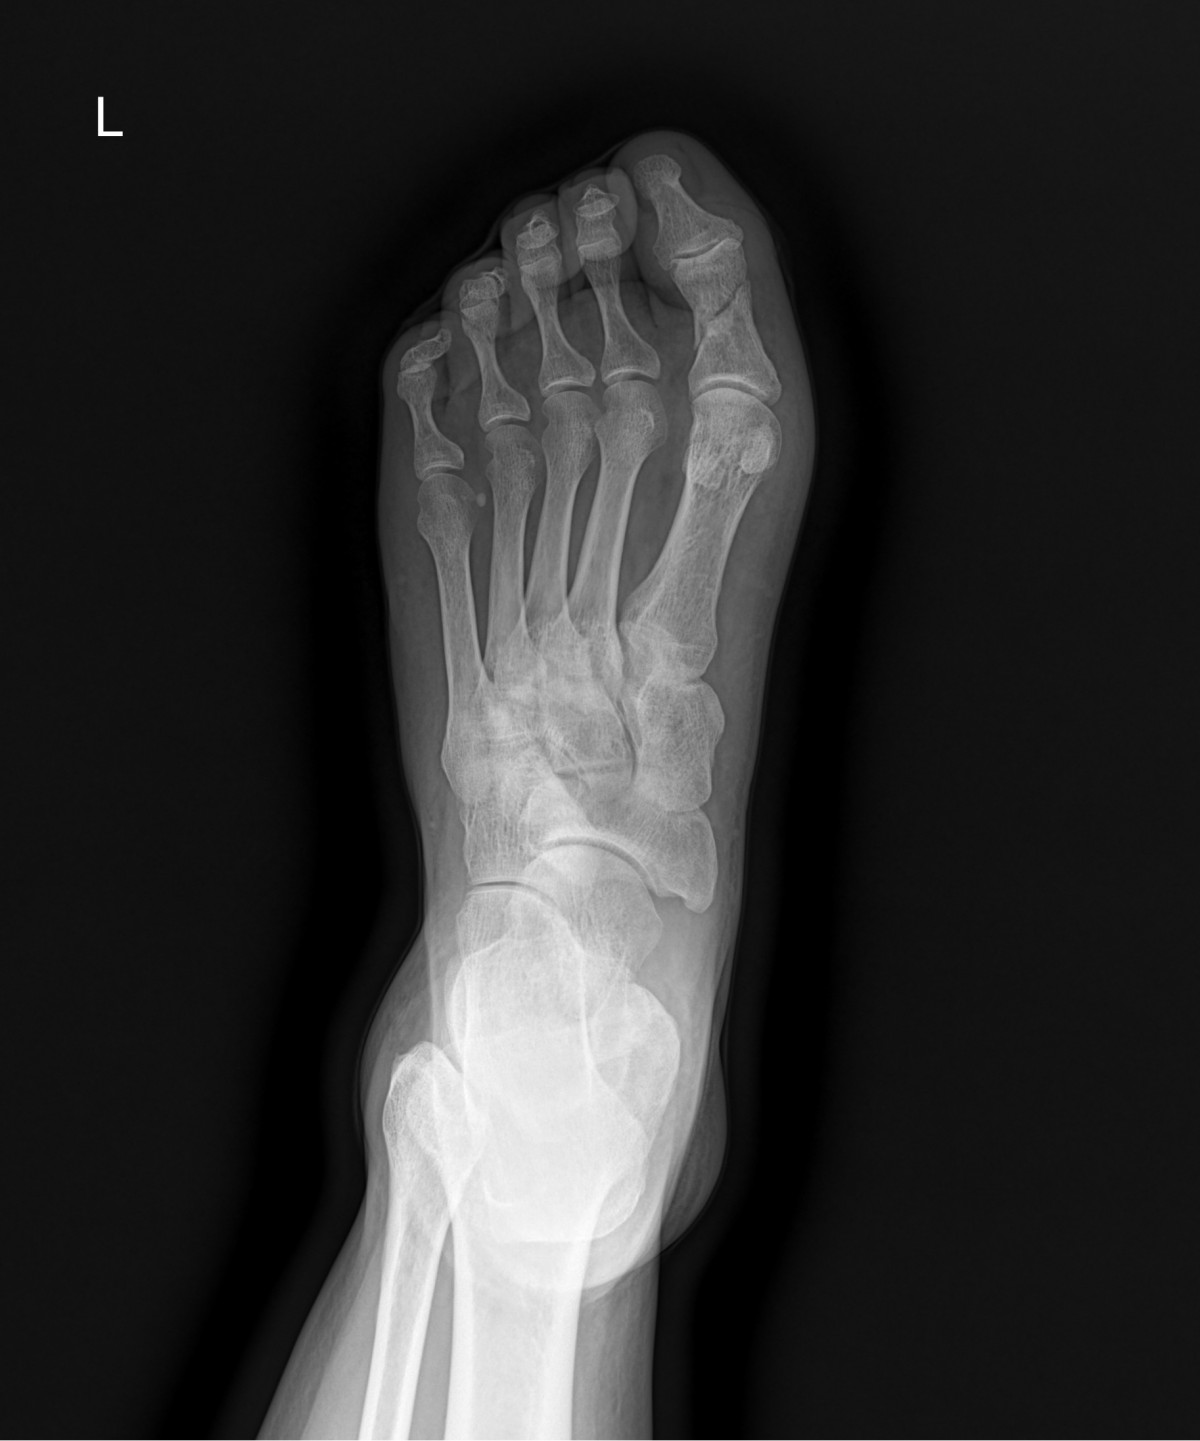

정지영원장님 발가락 골절 수술 강완O 환자

dae765e4d9ac96aee867c9d6292d8784_1758008742_5898.jpg